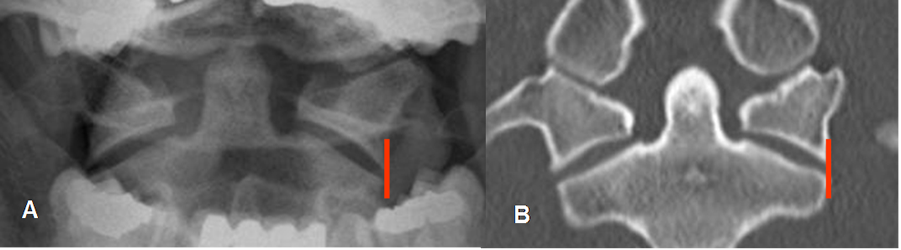

En la proyección de odontoides las masas laterales del atlas y axis, deben estar alineadas. Hasta 3 mm de desplazamiento lateral bilateral puede ser normal en los niños y 2 mm en los adultos. (38). (Fig 190).

Fig 190. Odontoides normal.

A: Rx AP y B: TAC reconstrucción coronal. Odontoides normal, con alineación de las masas laterales de C1 y C2.